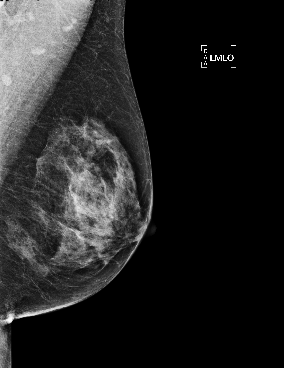

Based on these results, we submitted our final architecture described in Section 2 for testing on the large GH-Validation dataset. In the first sub-challenge, which records the AUC by breast purely on imaging and blinded to demographic information, we achieved AUC=0.879 (standard deviation: 0.00914), see Fig. 2(e), which is 0.005 above the top AUC in the competitive phase of the Challenge. It was also the highest single-model AUC in the collaborative phase, 0.014 below an ensemble of detection models, and higher than all patch-based models. The second sub-challenge is on subject-wise AUC, with access to both images and demographics. Despite ignoring demographics, our architecture gave AUC=0.868, behind only the top score in the competitive phase (a patch-based curriculum-trained model) by 0.006. Twenty-five method descriptions from this phase are available at synapse.org, but details of the collaborative phase, including performance of patch-based models trained on Optimam, is embargoed pending publication by the Challenge. Fig. 2 shows sample outputs from GH.

Refer to caption

Figure 2: (a) True positive prediction (p=0.90𝑝0.90p=0.90 probability of malignancy) of an inconspicuous lesion on a left MLO of a 73 year old woman. (b) True negative (malignancy: p=0.06𝑝0.06p=0.06) for left MLO view of a 66 year old woman. (c) False positive (p=0.78𝑝0.78p=0.78) on left MLO of a 43 year old woman, due to hyper-intense region. (d) False negative (p=0.03𝑝0.03p=0.03) for left CC view of a 61 year old woman. (e) ROC by breast, AUC = 0.879.